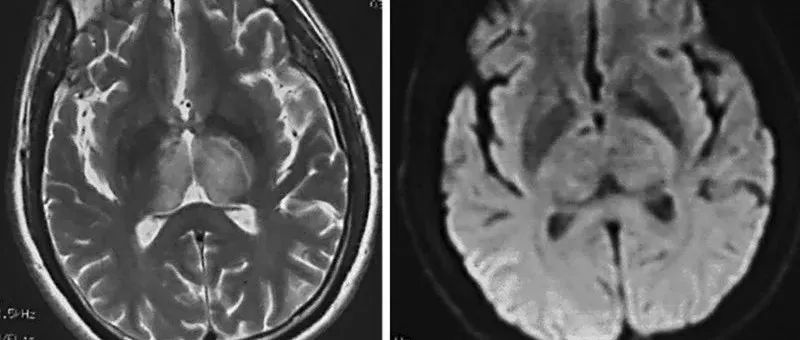

35岁女性,在2次右手局灶性感觉性发作后至医院就诊,其中第2次发展为全面性强直阵挛发作。查体未发现运动或感觉缺陷。MRI可见显示5个幕上病变,最大的2个为囊性病变——左侧中央后回上外侧30×30×32mm和右侧中央后回外侧7×9×6mm。所有病变均为T1低信号和T2高信号,周围有轻度血管源性水肿(图1A和C)。2个囊性病变呈周围强化、FLAIR高信号,且没有弥散限制(见图1B和D)。(图:MRI可见显示5个幕上病变,最大的2个为囊性病变——左侧中央后回上外侧30×30×32mm和右侧中央后回外侧7×9×6mm[A-D];病变呈T1低信号[A]和T2高信号,周围有轻度血管源性水肿[C];其在FLAIR上呈高信号[C],周围中度强化[B],无弥散受限[D];左侧中央后回上外侧病灶活检组织病理学显示脱髓鞘伴有囊性变和明显的星形胶质细胞增生[E],血管周围淋巴细胞成套[F],无残留髓鞘[G],CD163+巨噬细胞[H],以及大量反应性星形胶质细胞[I])...